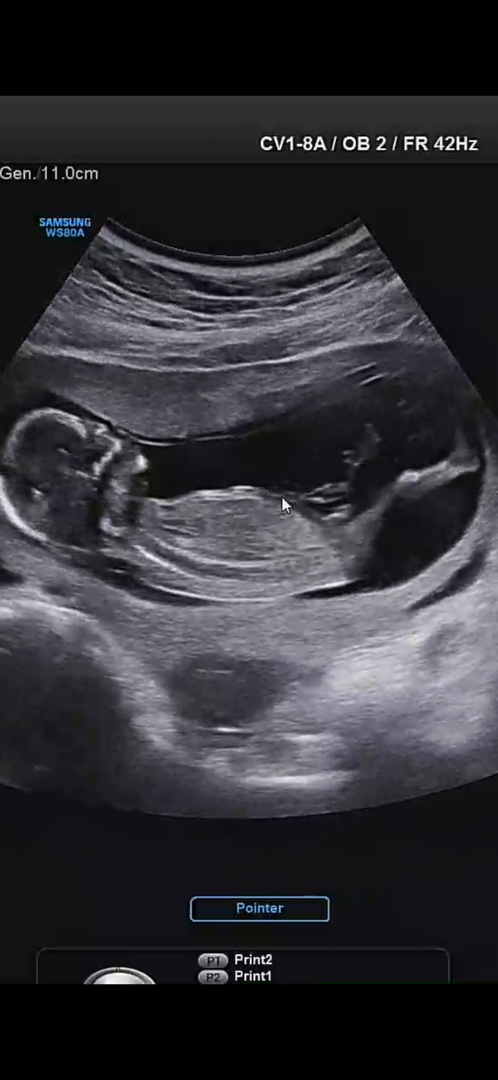

안녕하세요! 13주차 초음파 영상 중에 뭐가 보이는 듯한(?) 장면을 캡쳐했는데요! 각도법으로 봐야할지.. 아니면 다리 사이에 보이는 걸로 아들이라고 생각할 수 있을지 봐주시면 감사하겠습니다♥️♥️

아들같아요

저도 아들맘인데...!ㅎ 아들일거같아요..!